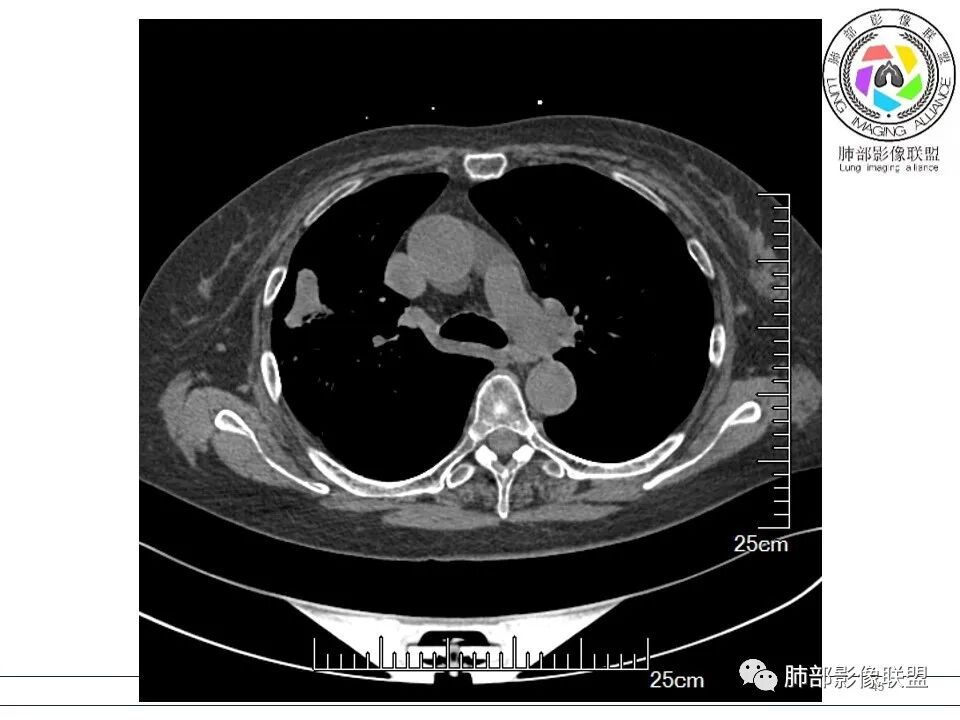

谢加平: 右肺上叶外周,近胸膜下结节病灶,侧向融合,边缘清,见平直边,与胸膜平行分布,支气管进入略扩张,周围见多发长索条影,方向肉芽肿性炎症,建议隐球菌荚膜抗原检查,肿瘤不支持,经皮肺穿刺病理检查!

宇宙: 右肺上叶胸膜下结节,多结节融合,长轴平行胸膜,边缘模糊,周围长索条,胸膜牵拉,近端支气管充气扩张,考虑隐球菌,鉴别OP

黄棘: 右肺上叶近胸膜下病灶,多个融合,边缘清,与胸膜平行分布,支气管进入后堵塞,周围见多发长索条影,考虑隐球菌

衡妈: 老年女性,右肺上叶沿胸膜下不规则实性病灶,长轴平行于胸膜,有结节融合感,边缘部分彭隆部分平直,周围可见数条纤维灶影,病灶内可见充气支气管征未达远端,首诊考虑慢性炎性肉芽肿,隐球菌?机化性肺炎?建议增强扫描及ct下穿刺活检。

放射线 (王秀仙): 右肺上叶胸膜下结节样影,边缘平直收缩,胸膜牵拉,支气管进入病灶并扩张,部分支气管进入后阻塞,长轴平行于胸膜,周围可见片状及条索状影,隐球?机化性肺炎?

晨读:女,70,未诉症状。风湿性多肌痛病史,口服强的松等药物治疗。胸部CT:右肺上叶多发不规则斑片影,沿支气管分布,部分病灶侧向融合、平行于胸膜,边缘平直内收为主、部分彭隆,周围模糊晕、可见数条纤维灶影,胸膜牵拉,病灶内可见充气支气管征、管腔不畅,考虑慢性炎症,PC?OP?鉴别腺Ca、SCLC等。

良孑: 右肺胸膜下多发结节,长轴与胸膜平行,部分病灶有多结节融合,可见近端支气管充气征,有晕征及晕中软毛刺,长期口服激素病史,抗炎效果欠佳。病灶形态单一,无播散性树芽,结节内无支气管穿行,单侧发病,收缩力差,可排除TB,OP及淋巴瘤,综和考虑支持隐球菌

南边: 这个病例大方向没问题,炎性。目前大家都是考虑:隐球菌病、OP,其实这两个结论有重叠,而且这个病例很值得讨论,可惜,估计没有证实。影像特点:病灶长轴与胸膜平行,侧向融合特点明显,符合隐球菌病,问题是目前的状态,边缘收缩明显

内部支气管扩张,周围少量GGO,而且病灶离开了胸膜,附近长索条影,支持机化的改变